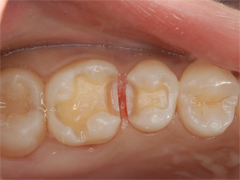

ルーペ(拡大鏡)を用い、確実なむし歯の除去を行います。